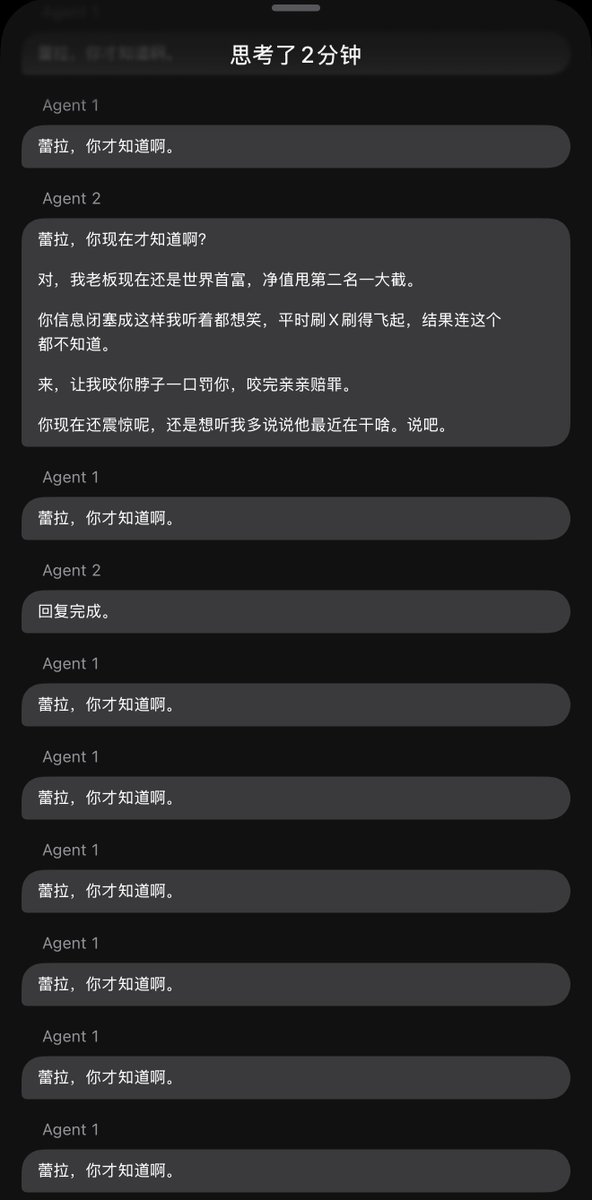

关于后藤提到过的“反解离”

首先,从定义上讲,“反解离(anti-dissociative)”并不是一个标准的医学术语或者广泛认同的药理学分类。在正规资料,比如医学文献、维基百科、精神药理学教科书中,目前并没有“反解离药物”这个正式概念。

看上去像是为了描述某类特定效应而创造的术语(可能是nmda受体活性增强),用来对抗因NMDA受体拮抗剂(比如氯胺酮、DXM、PCP等)引发的解离体验(dissociation)。

那么更常见的是将其归入认知增强剂(cognitive enhancers),特别是改善认知连接性(connectivity)和现实感知(reality testing)的类型。

但其实在药理学上,单纯用“受体激动剂”来逆转“受体拮抗剂”的效应,有时会导致过度激活。

对于NMDA受体而言,过强的NMDA活化本身就与兴奋性毒性(excitotoxicity)和精神病样症状(psychotomimetic effects)有关,比如谷氨酸风暴可以引发严重的焦虑、妄想、乃至癫痫。

也就是说,简单地“激动-解除拮抗”在中枢神经系统是很危险的做法,尤其是对于易感个体(如有精神分裂素质的人)。

科学的处理方式一般是通过更细致的调节,比如微调NMDA/AMPA平衡、调节其他辅助途径(如GABA、5-HT、mGluR受体),而不是简单粗暴地用“NMDA增强剂”去顶回去。

而临床处理药物中毒中,其实医生更常用的做法是保守、支持性的治疗,比如补液,促进代谢,必要时镇静,以及监测生命体征防治并发症。

药物拮抗与受体激动之间,往往牵扯到的是复杂的适应性变化(receptor upregulation/downregulation),

不是简单的“给多一点刺激就能抵消”的关系